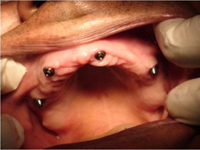

Bezzubá čelist je hlavní indikací pro ošetření pomocí implantátů. Zejména celkové zubní náhrady v dolní čelisti mají velice nízkou stabilitu a držení díky velkému úbytku kosti.

S pomocí zubních implantátů můžeme díky různým kotevním systémům (třmeny, kulové hlavy, Locatory) zajistit stabilitu a držení protézy nebo při použití většího počtu implantátů zhotovit pevné náhrady – můstky nalepené nebo našroubované na pevno na implantáty.